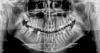

Stanis777 Опубликовано 27 июля, 2010 Поделиться Опубликовано 27 июля, 2010 Добрый день, мне 25 лет. Просьба к тем кто в этом разбирается. Прокомментируйте пожалуйста панорамный снимок на предмет патологических изменений (кисты, воспаления и т.п.), если они есть. Ссылка на комментарий

Снежана Опубликовано 28 июля, 2010 Поделиться Опубликовано 28 июля, 2010 все восьмерки удалять, все депульпированные, кроме того, что под коронкой нужно перелечить. Ссылка на комментарий

Большой Зеленый Опубликовано 28 июля, 2010 Поделиться Опубликовано 28 июля, 2010 все восьмерки удалять, все депульпированные, кроме того, что под коронкой нужно перелечить.28 и 48 я бы оставил. Про лечение согласен. Вижу гайморит .Предполагаю что одонтогенный. Ссылка на комментарий

Aldo Rain Опубликовано 28 июля, 2010 Поделиться Опубликовано 28 июля, 2010 чтобы точно увидеть все свои проблемы и оценить полную картину состояния своих зубов рекомендуется сделать компьютерную томограмму челюстей. На сегодняшний день это вполне доступно. Все грамотные специалисты при такой ситуации как у вас начинают диагностику именно с просмотра дентальной томограммы. Все "мертвые"зубы подлежат перелечиванию, все 8-ки надо удалить. +1 Снежане. По поводу левостороннего гайморита на этом снимке четко ничего не видно, надо смотреть КТ челюсти. Ссылка на комментарий

Снежана Опубликовано 28 июля, 2010 Поделиться Опубликовано 28 июля, 2010 28 и 48 я бы оставил. Про лечение согласен. Вижу гайморит .Предполагаю что одонтогенный.28 без антагониста, затрудненное очищение, послезавтра в нем будет пульпит и удаление по острой боли, можно подождать, можно удалить планово, не дожидаясь)48 - ну... может быть и так, во рту смотреть нужно Ссылка на комментарий

Maximvs Опубликовано 28 июля, 2010 Поделиться Опубликовано 28 июля, 2010 слева сверху 5 и 6 - вроде есть изменения вокруг корней. Может быть от них и гайморит (слева) ТОчнее можно сказать по компьютерной томограмме. Ссылка на комментарий